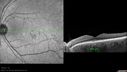

Acute Central Serous Retinopathy - Infra-red image shows area of vision loss

Acute Central Serous Retinopathy - CSR - Steroid Induced (probably) - Good Vision - 6 months later - vision Better577 views42-year-old man has central serous retinopathy in the right eye with serous retinal detachment. 6 month follow-up Vision is better.OD 20/20. The patient looked at this infra-red image and said "That's exactly what I see!"

Acute Central Serous Retinopathy - CSR - Steroid Induced (probably) - Good Vision - 6 months later - vision Better INFRARED SHOWS EXACT VISION DEFECT707 views42-year-old man has central serous retinopathy in the right eye with serous retinal detachment. 6 month follow-up Vision is better.OD 20/20. The patient looked at this infra-red image and said "That's exactly what I see!"     (0 votes)

FUNDUS PHOTOGRAPHY - INFRA RED: The image does show where the serous detachment was.